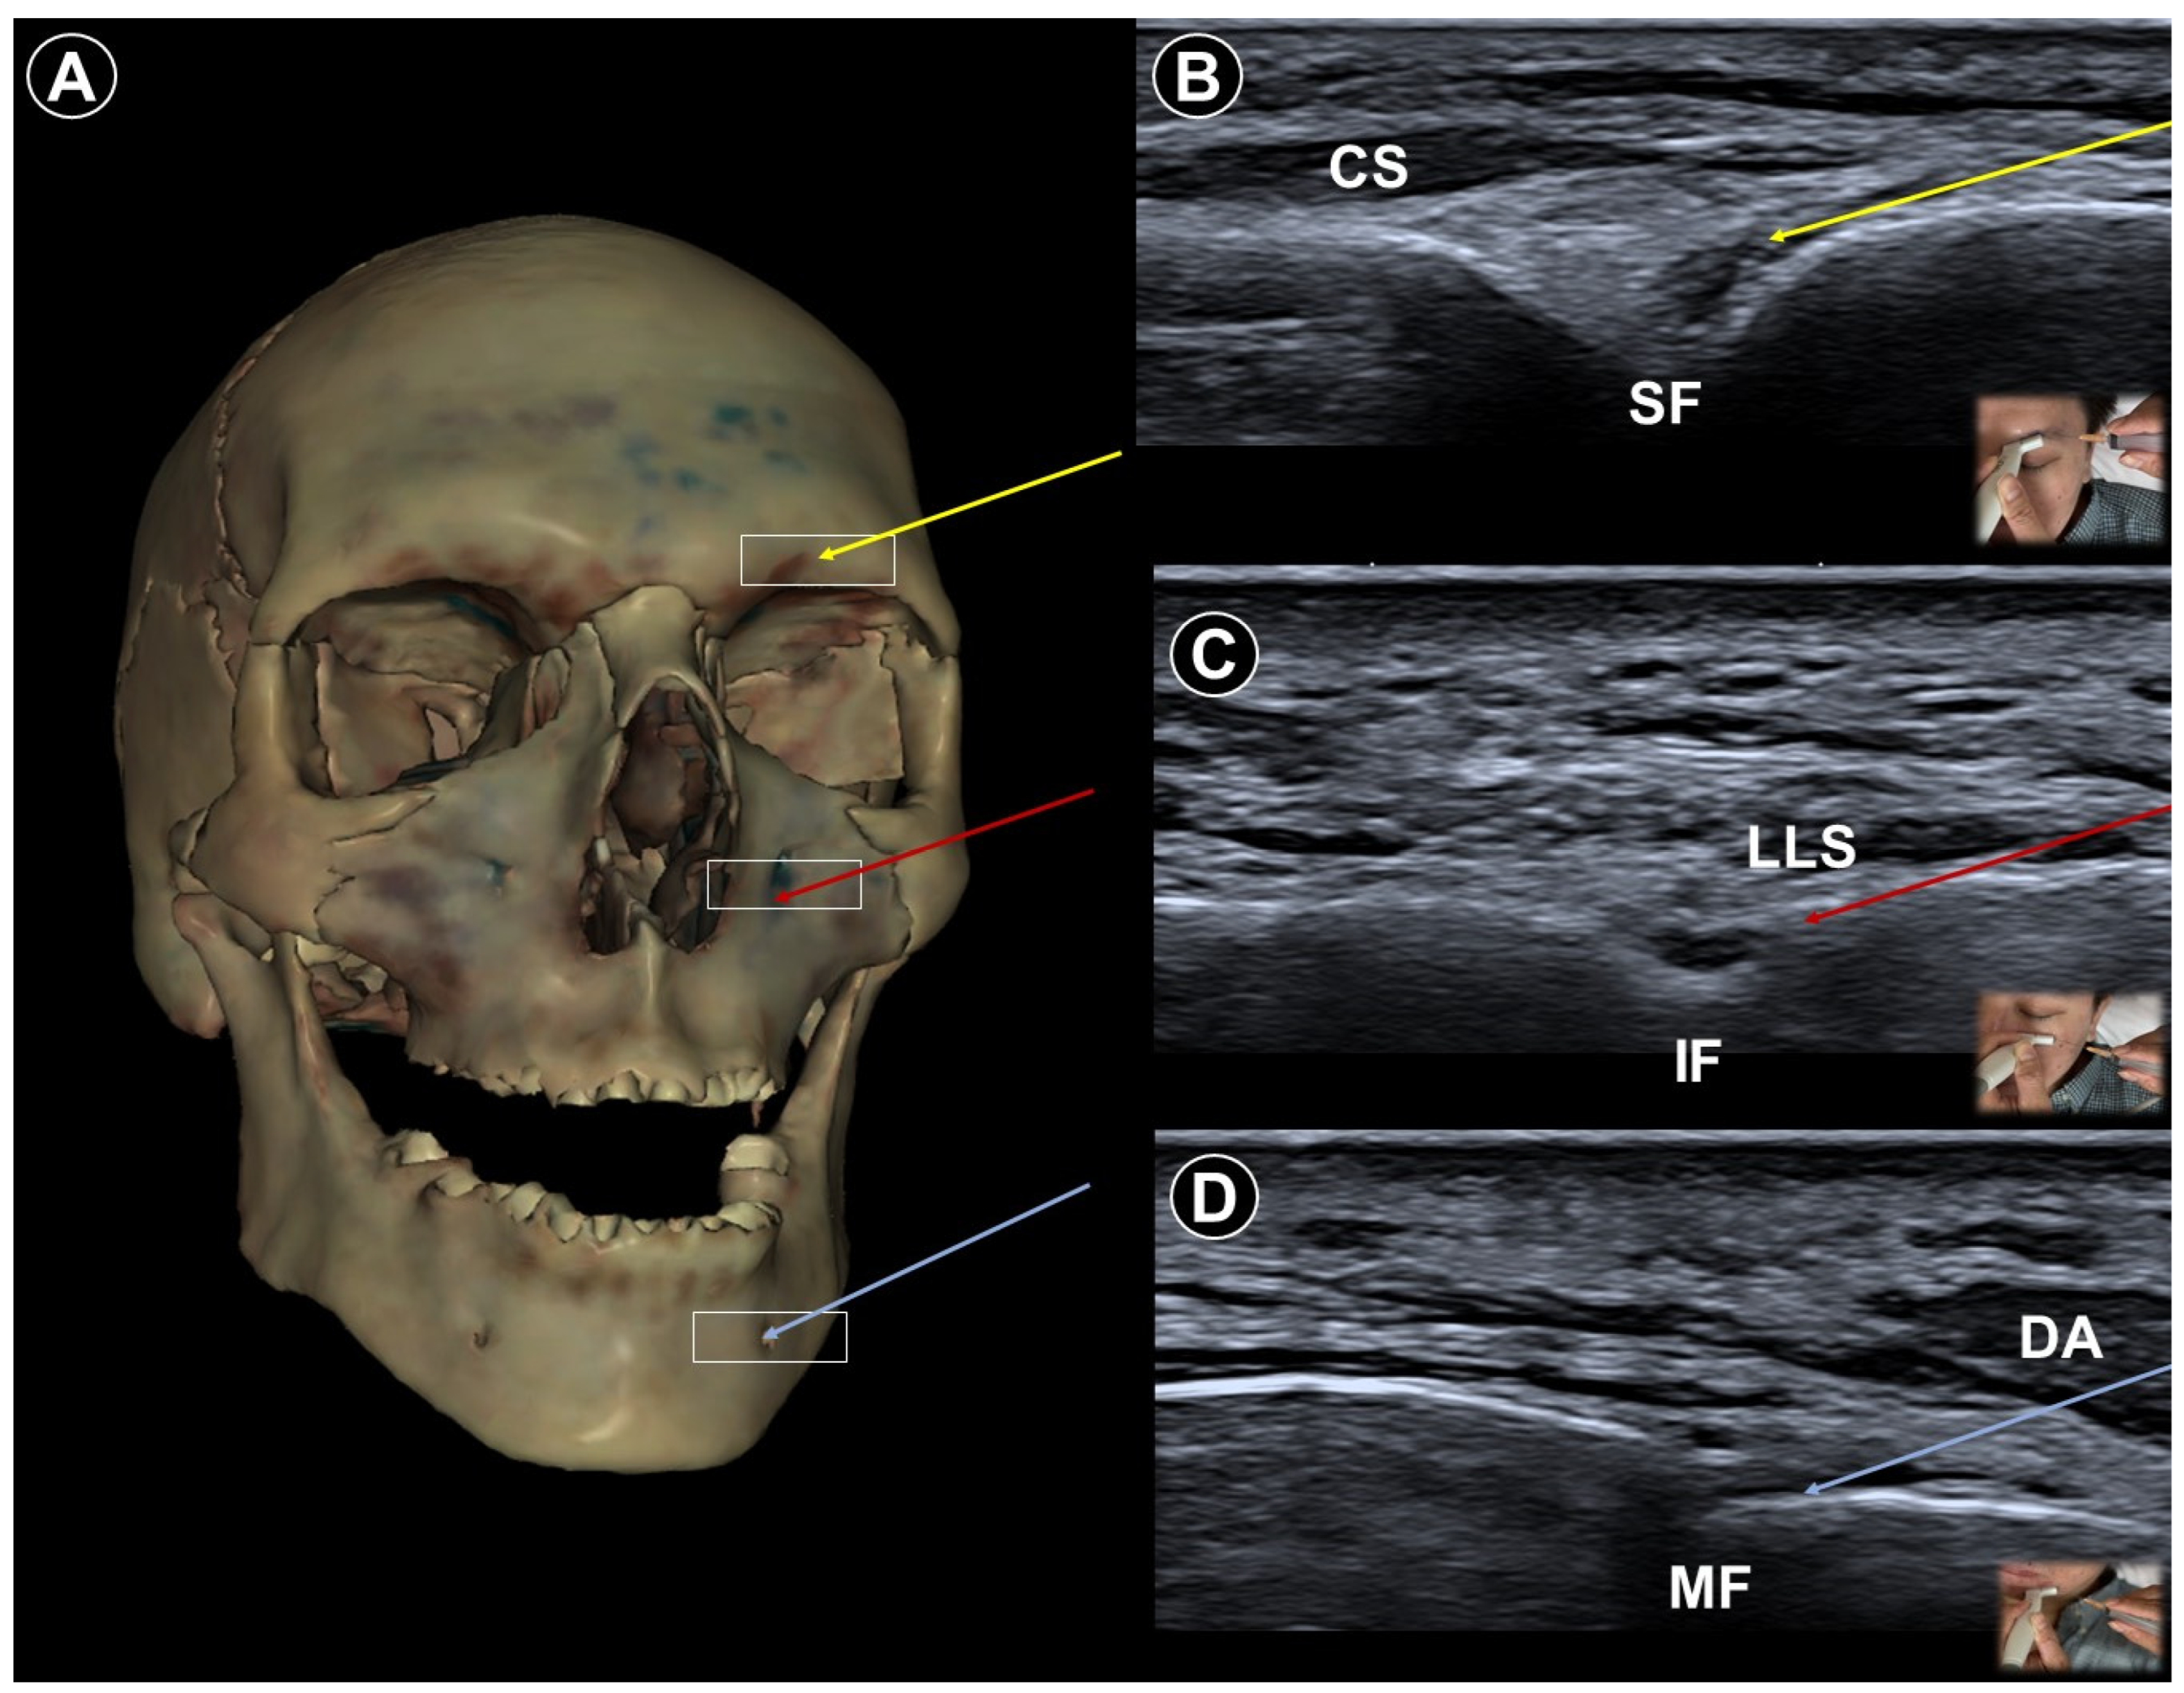

- Allam, A.E.; Khalil, A.A.F.; Eltawab, B.A.; Wu, W.T.; Chang, K.V. Ultrasound-Guided Intervention for Treatment of Trigeminal Neuralgia: An Updated Review of Anatomy and Techniques. Pain Res. Manag. 2018, 2018, 5480728. [Google Scholar] [CrossRef]

| Trigeminal neuralgia | Paroxysmal facial pain in one or more divisions of the trigeminal nerve | Neurovascular compression at root entry zone | Head neutral | Linear probe, in-plane

| Sustained pain relief by nerve block (case study) | Use Doppler imaging to avoid vascular puncture |